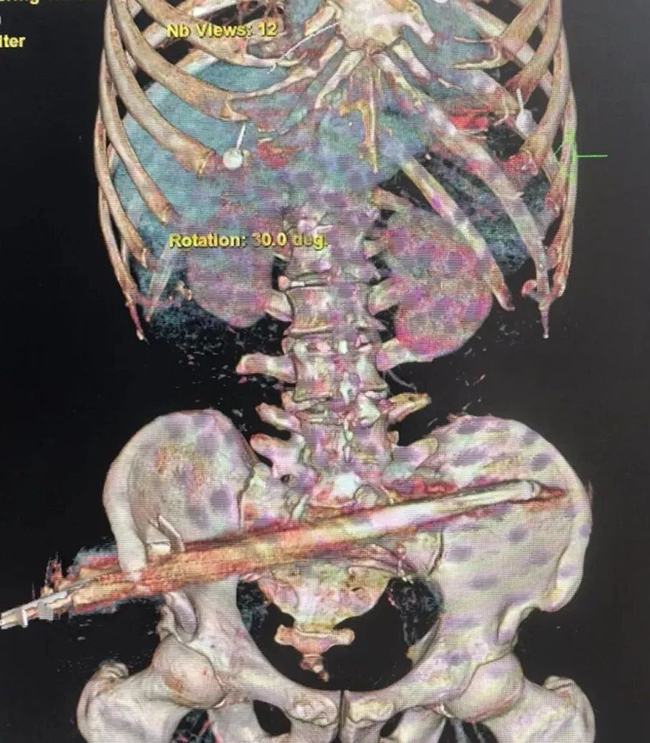

12月26日下午,伴随着急促的鸣笛声,一辆120救护车飞速驶入我院。车上的李先生因施工时不慎从1.8米高处坠落,被地面竖立的钢筋从臀腹部径直贯穿。时间就是生命,“启动创伤救治绿色通道!”早已待命的急诊医学中心团队迅速响应。“必须尽快明确钢筋在体内的走行路径,排查大血管及重要脏器损伤情况!”沈丛林果断表示,患者被迅速转运至CT室。

影像结果揭示了双重危机:钢筋经右侧骨盆区穿入,造成髂骨粉碎性骨折、小肠破裂、肠系膜损伤,所幸避开了腹主动脉等致命要害,然而,一个意料之外的发现让救治团队心头一紧:肝右叶赫然存在一个巨大占位,高度怀疑为恶性肿瘤。这根外来的钢筋,竟意外揭示了体内一个更为隐秘的“杀手”。